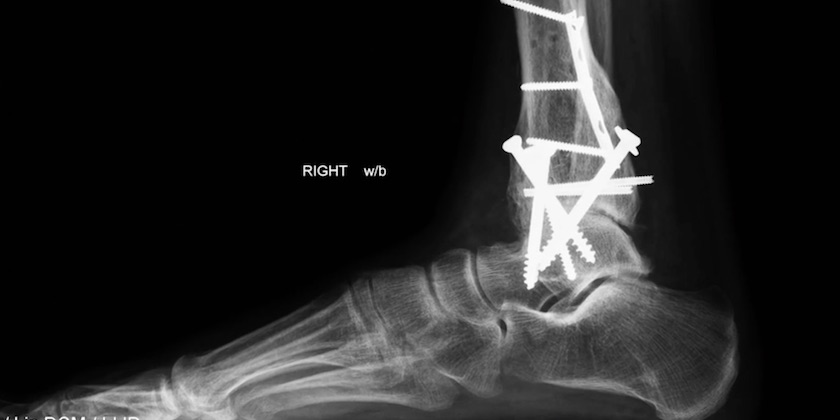

Here’s closeup of the fustercluck:

Kind of gives me the feeling UW Medical School’s motto is ‘If at first you don’t succeed, try, try again. Don’t give up. Do it again, with gusto. I had no idea you could get that much metal inside such a small area. It also confirms my belief in having a good FTCA law that protects us against this kind of insanity. Seeing’s how the Seattle VAMC is so sloppy, perhaps you might want to keep the attorney’s number close at hand for any of Seattle’s future medical misadventures. Mr. James Holman Esq. is right next door to my favorite restaurant.